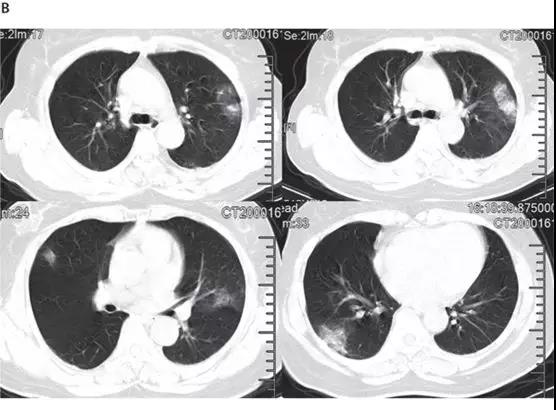

ICU患者入院时胸部CT图像的典型发现,是双侧多发小叶和亚段实变(见下图)。